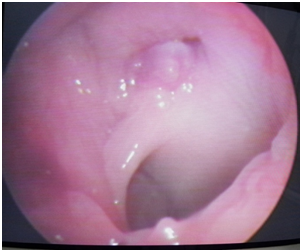

Before shifting patient to operation theatre, a repeat MR Angiography was done to ensure that there is a stable thrombus at the injury site before pack removal. It showed an ill defined hypodense areas involving gray and white matter in left frontal and parietal lobes in the region of ACA-MCA and MCA-PCA watershed territories respectively, suggestive of watershed territory infracts. Ill defined hypodense areas suggestive of infracts are seen in left centrum semiovale in vicinity of central sulcus (Figure 2) and loss of signal intensity in petrous, cavernous and supraclival part of left ICA (Figure 3). Nasal pack removed under GA with no re-bleeding from injured site. Clot was seen over the injured part of ICA in the left sphenoid sinus plugging the LT ICA (Figure 4). Postoperative antiplatelet therapy continued augmented with physiotherapy.

Figure 4 ICA Clot after immediate removal of nasal packing.